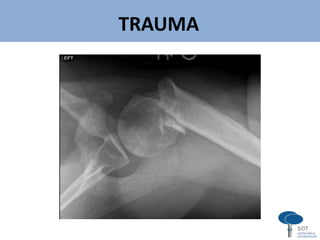

Luxação aguda

Instabilidade glenoumeral